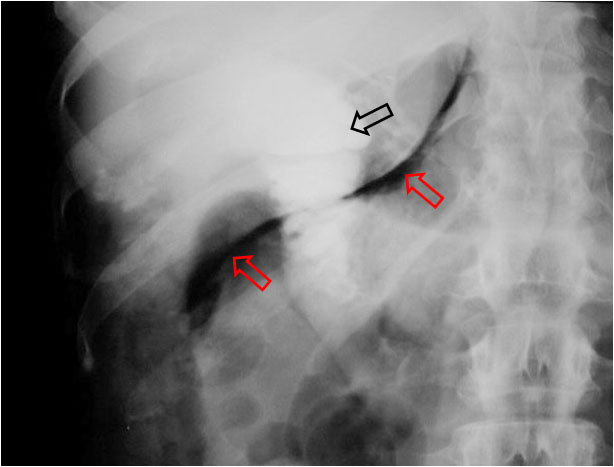

Signo de neumoperitoneo en la radiografía simple de abdomen. Se aprecia una colección aérea lineal (como la que marcan las flechas rojas en la imagen) o triangular que se dispone de inferolateral a superomedial. Si es triangular, la colección aérea presenta una morfología cóncava superolateralmente (ver Signo del Duce). Se cree que las colecciones lineales representan gas en el espacio subhepático derecho mientras que las triangulares reflejan la presencia de gas a nivel del receso posterior del espacio subhepático (saco de Morison).

La imagen corresponde a una perforación duodenal en el transcurso de una CPRE con papilotomía, de ahí la presencia de contraste en la vía biliar y en el duodeno (flecha negra).